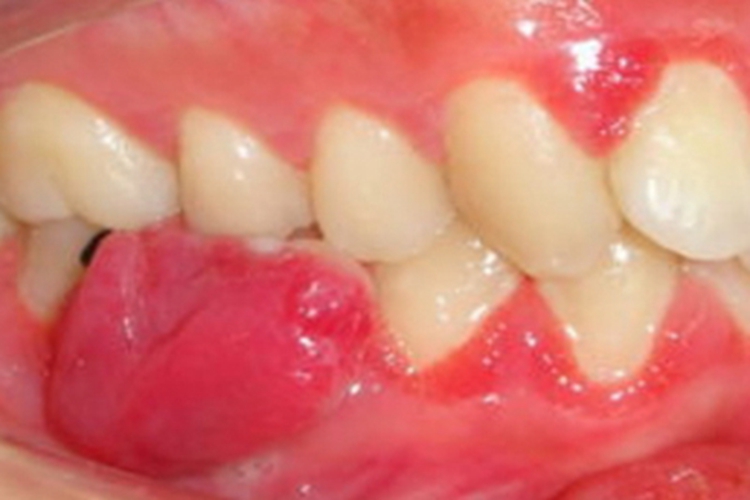

妊娠期龈瘤可导致牙龈出现局限性的无痛性肉球样皮损,呈鲜红色,质松软,无蒂,体积较大时可遮挡牙齿,容易在触碰后出血,随病情发展,生长迅速。

妊娠期龈瘤治疗上应由医生去除一切局部刺激因素,如菌斑、牙石、不良修复体等,操作时要特别仔细,动作轻柔,尽量减少出血;牙龈肿胀肥大明显、龈袋有溢脓时,可用过氧化氢溶液冲洗或含漱,尽量避免使用药物治疗,以免影响胎儿发育;对于体积较大的妊娠期龈瘤,若已妨碍进食时,可手术切除,手术尽量选择在妊娠期的4-6个月,以免引起流产或早产。